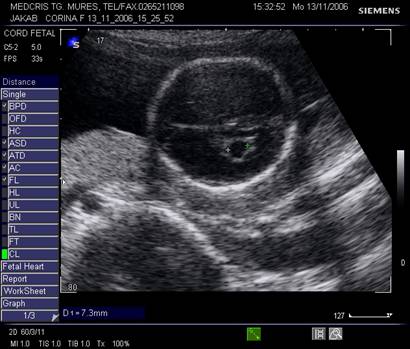

Fig . nr. 248. Chist de plex choroid , unilateral, la o sarcina de 17 sapt.